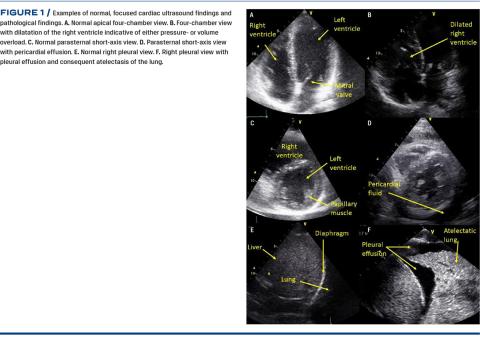

FOCUS follows the principle formulated in the focused assessed transthoracic echocardiography (FATE) protocol [8]. In short, FOCUS provides information on cardiac status and pleural effusion by the following views: Apical four-chamber view, apical five-chamber view, parasternal long-axis view, parasternal short-axis view, subcostal four-chamber and inferior vena cava view, and bilateral pleural views. See Figure 1 for examples of normal anatomy and common pathology. Two-dimensional grey-scale cine loops are stored from each view and the data extracted are fed into the web-based REDCap (Research Electronic Data Capture) data capture tool [17]. The data extracted are based on visual evaluation of cine loops including eye-balling, simple calibration and M-mode. Activation of Doppler modalities are not allowed. The data from each view are synthesised to automatically generate a FOCUS report that is made available to the anaesthesiologist ultimately responsible for providing anaesthesia to the patient. Please see Figure 2 for a FOCUS report example. The report contains information on:

The specific criteria for generating the individual components of the FOCUS report are given in Figure 3.